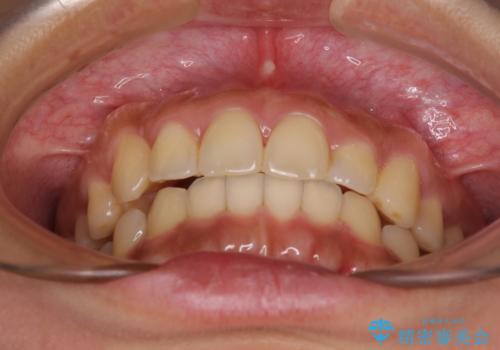

【モニター】歯列が狭くデコボコが気になる 急速拡大装置を用いたインビザライン矯正

上下の骨幅を改善したことで、スムーズに歯列矯正を行うことができました。

土台のまま放置されていた歯は土台の状態で咬み合っていましたが、急速拡大を行った際に咬み合わせが著しく挙上されたため、その際に土台を大きくすることで咬み合う歯との距離を確保しました。